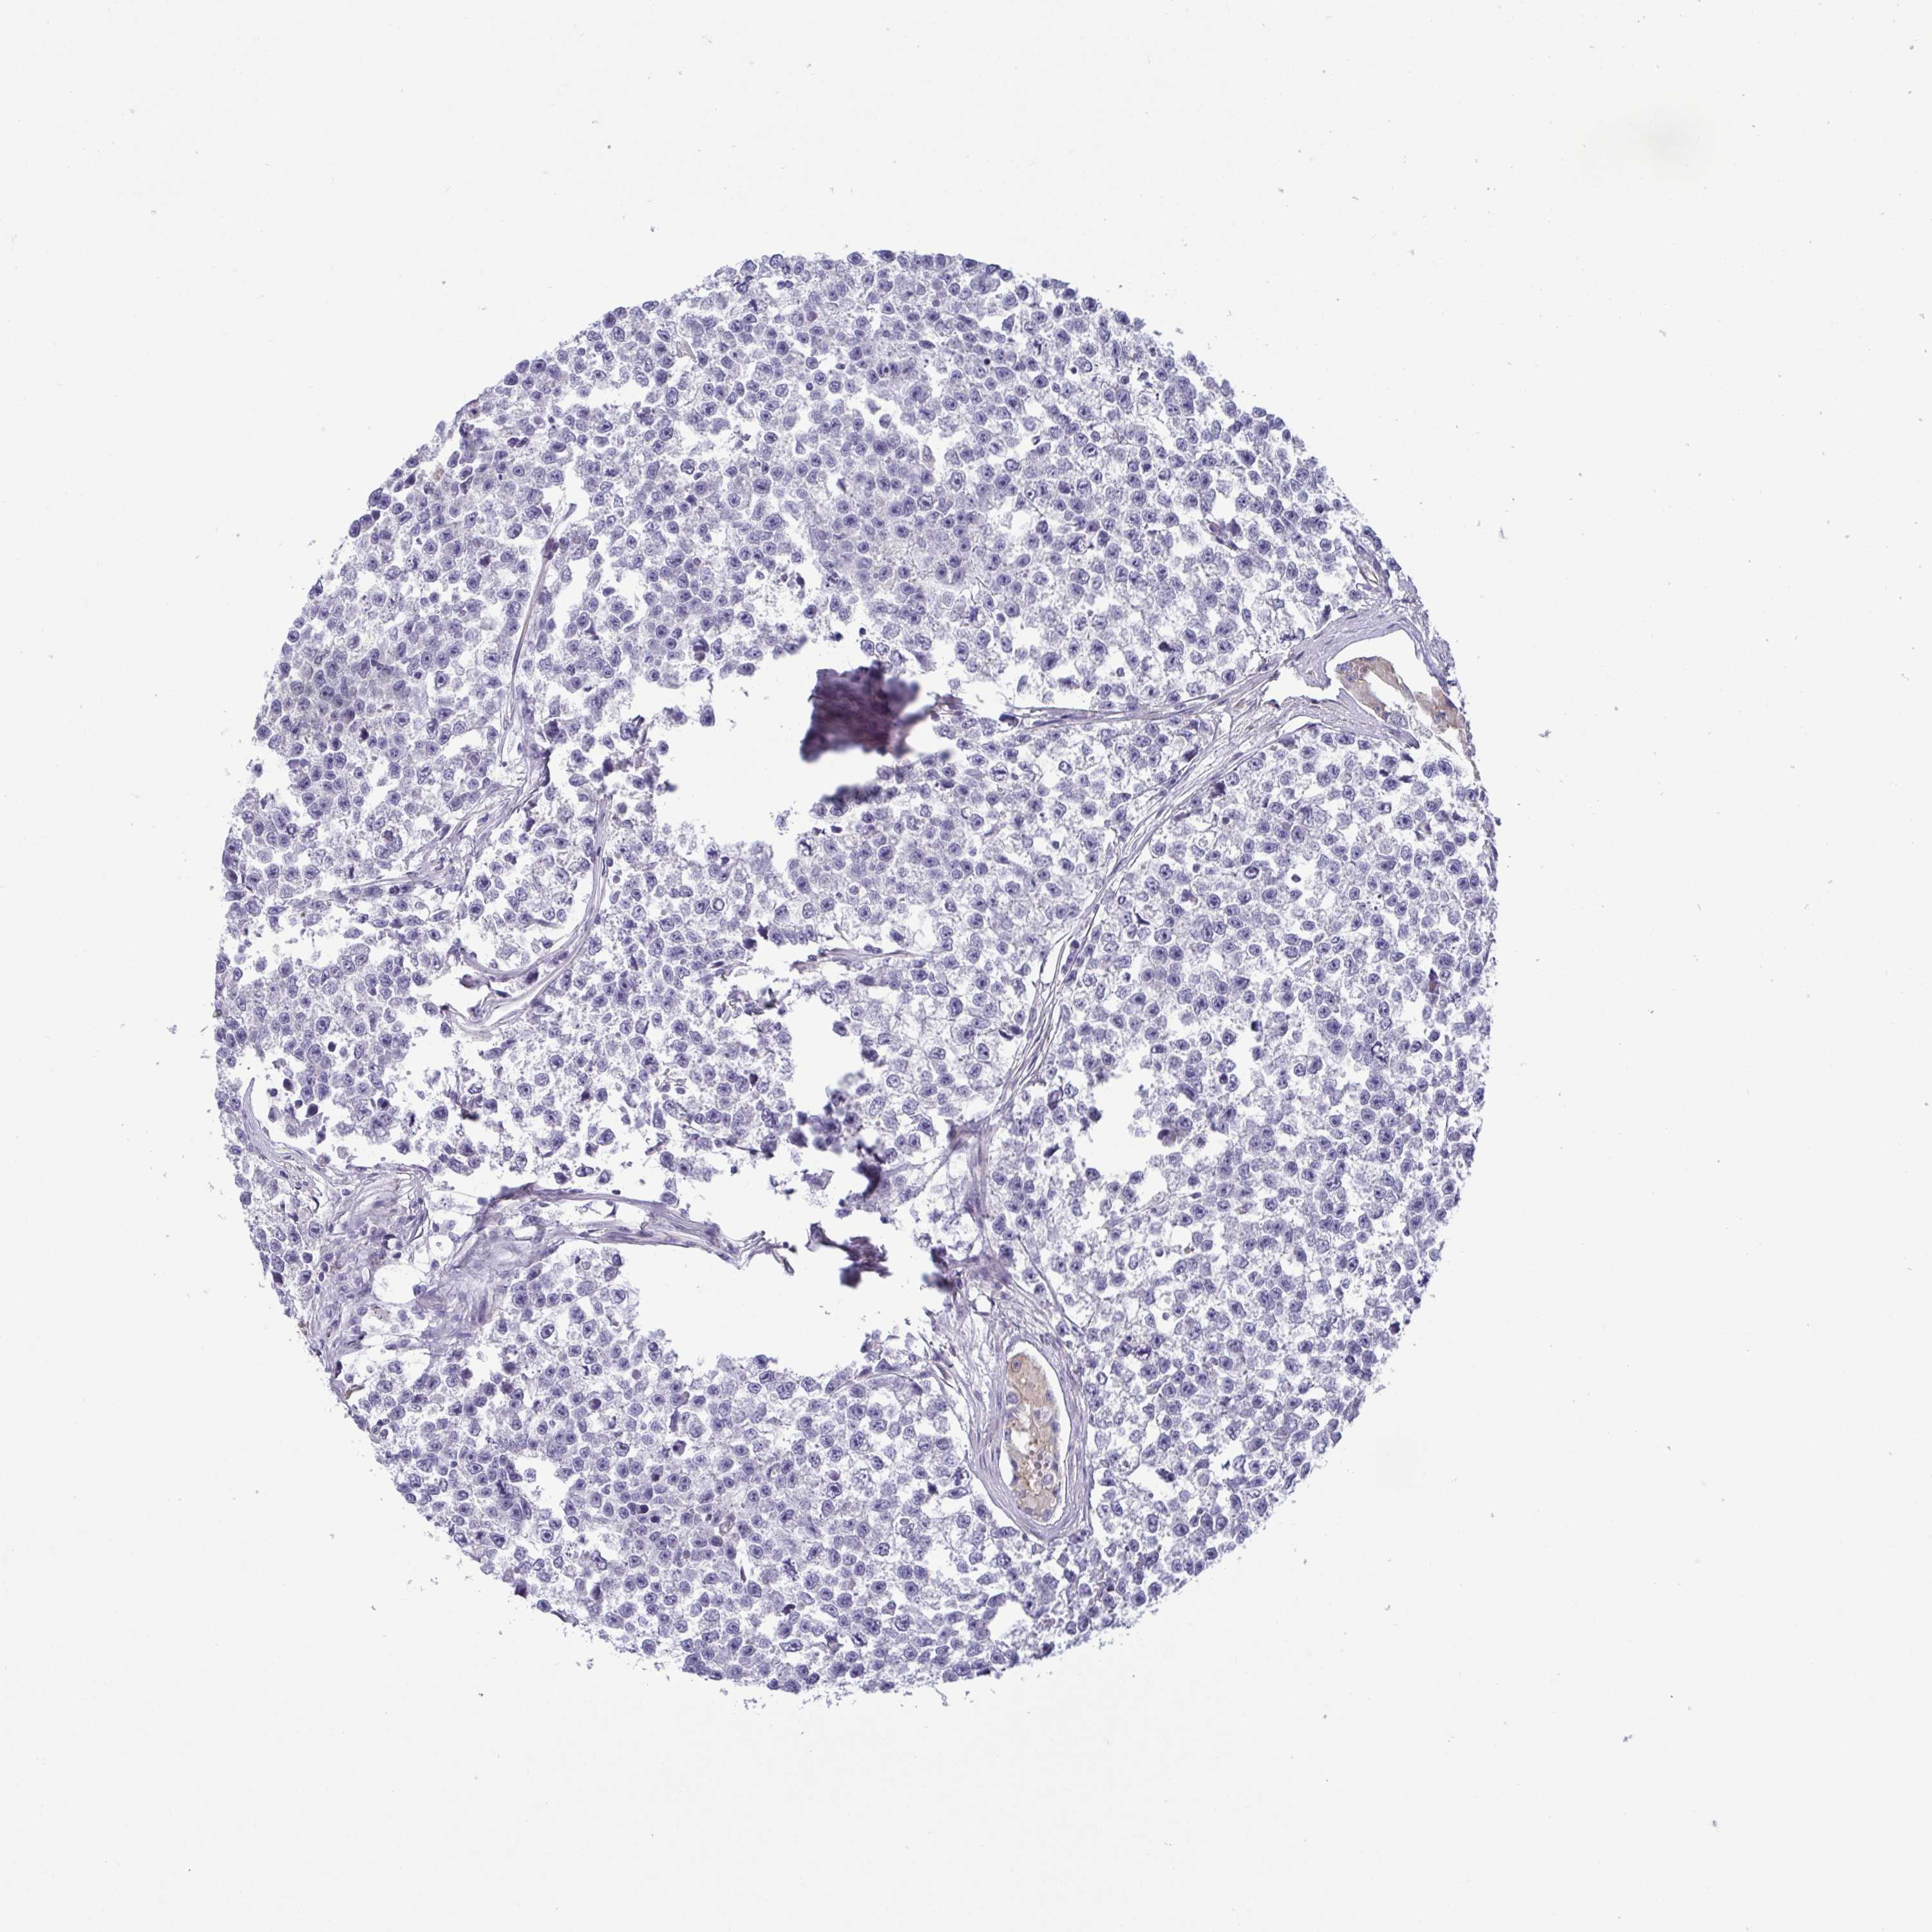

TESTIS CANCER - Protein expressioni

A mouse-over function shows sample information and annotation data. Click on an image to view it in a full screen mode. Samples can be filtered based on level of antibody staining by selecting one or several of the following categories: high, medium, low and not detected. The assay and annotation is described here.

Note that samples used for immunohistochemistry by the Human Protein Atlas do not correspond to samples in the TCGA dataset.

Antibody stainingi

Antibody staining in the annotated cell types in the current human tissue is reported as not detected, low, medium, or high, based on conventional immunohistochemistry profiling in selected tissues. This score is based on the combination of the staining intensity and fraction of stained cells.

Each image is clickable and will lead to virtual microscopy that enables deeper exploration of all samples and also displays staining intensity scores, fraction scores and subcellular localization as well as patient and tissue information for each sample.

Antibody HPA062626

Staining

High

Medium

Low

Not detected

Intensity

Strong

Moderate

Weak

Negative

Quantity

>75%

75%-25%

<25%

None

Location

Nuclear

Cytoplasmic/membranous

Cytoplasmic/membranous,nuclear

Teratoma, malignant, NOS